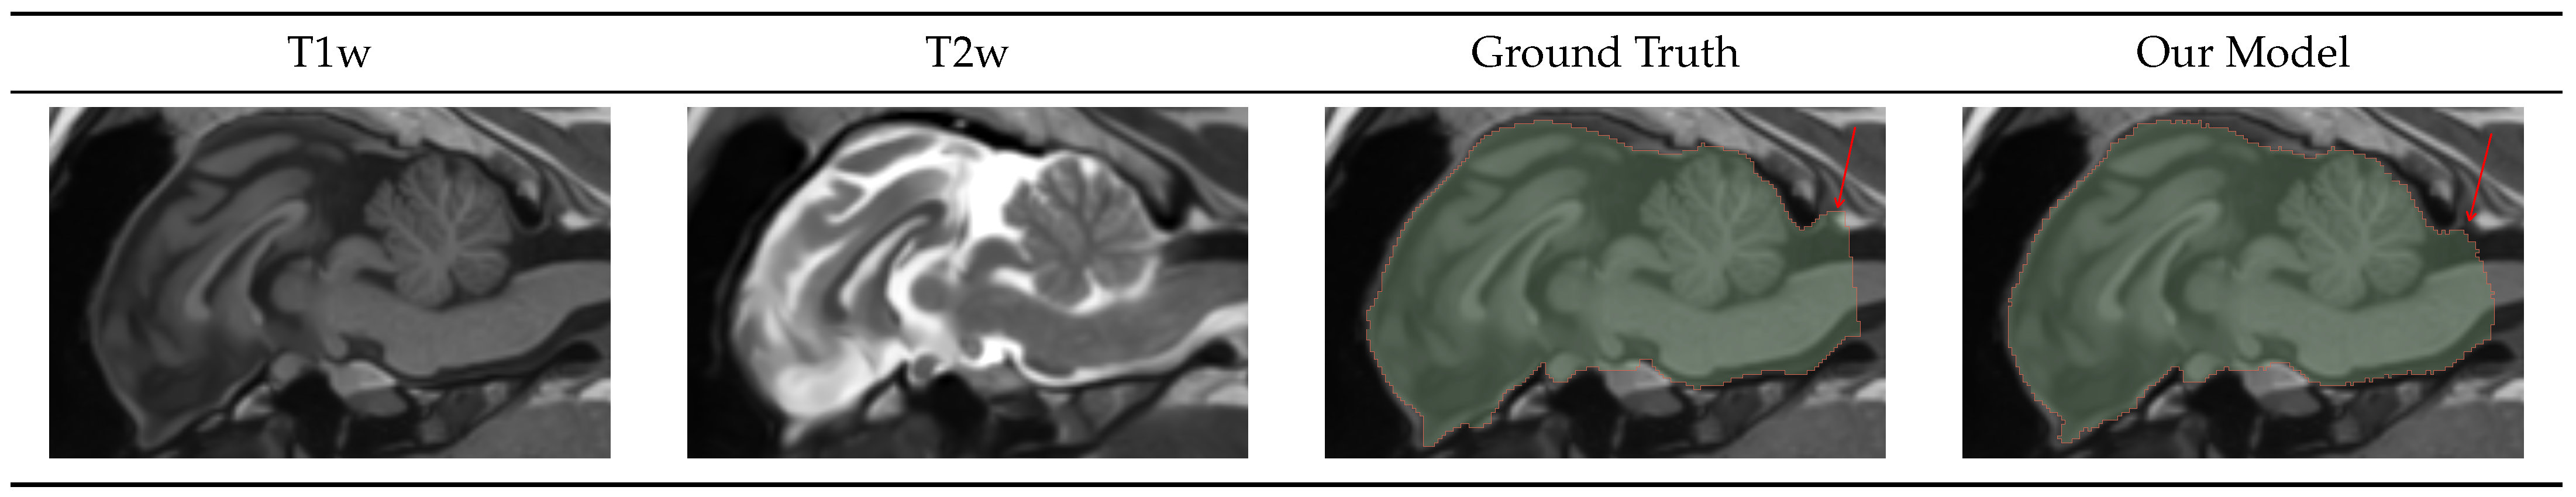

4.1.2. Intracranial Volume Mask

Figure 3 shows the input T1w and T2w images, the ground truth, and the predicted ICV mask. As can be seen in Table 4, the ICV model was more accurate and consistent than the high-resolution model at a DICE of 0.98, with a standard deviation of 0.003 and bAVD of 0.03 voxels and a standard deviation of 0.004 voxels. Furthermore, those numbers were negatively impacted by the posterior mask cutoff differences, indicated by the red arrow.

Figure 3.

Intracranial volume mask visualization. Using both T1 and T2 weighted images simultaneously, our model generated exceptionally high-quality masks that only differed from the ground truth in the posterior cutoff point, indicated by the red arrow.